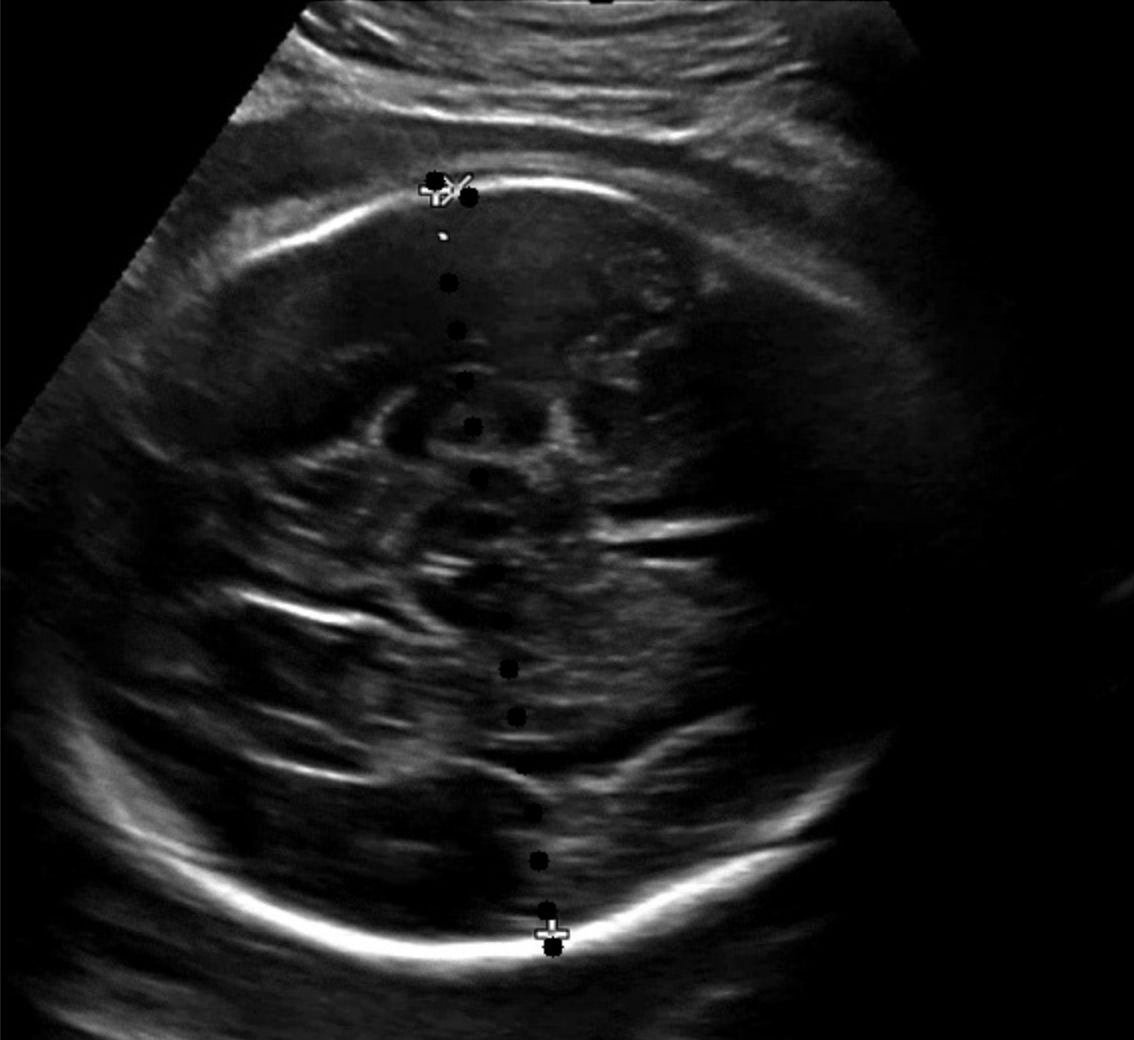

점선 패턴을 활용한 두개골 인식에서 대부분의 경우 안정적으로 좌표를 추출할 수 있었지만, 간혹 좌표값이 튀는 이상치 (outlier) 가 발생하는 사례를 확인했다. 이는 점선 패턴이 이미지의 특정 영역에서 명확히 인식되지 않거나, 노이즈로 인해 잘못된 좌표가 포함되는 경우였다. 아래 이미지와 같은 경우에서 좌표값이 연속되지 않고 불규칙하게 분포하거나, 특정 축(x 축 또는 y 축)을 기준으로 값이 급격히 변화하는 사례가 대표적이었다.

이를 해결하기 위해 처음 시도한 방법은 연속된 좌표의 기울기를 분석하여 같은 기울기를 가지지 않는 좌표를 이상치로 간주하고 필터링하는 방식이었다. 이 방법은 일정 부분 효과적이었지만, 초음파 이미지의 특성상 점선 패턴이 부분적으로만 인식되는 경우, 즉 점선 일부가 끊겨 있거나 불완전한 형태로 나타나는 경우에는 오히려 유효한 좌표까지 제거되는 부작용이 발생했다. 특히 점선이 희미하게 보이는 저품질 이미지에서는 이 문제가 두드러지게 나타났다.

이를 보완하기 위해 좌표 클러스터링 (clustering) 기법을 도입했다. 우선, x 축을 기준으로 tolerance (허용 오차) 내에 위치한 점들을 하나의 클러스터로 그룹화하고, 각 클러스터의 크기를 비교하여 가장 큰 클러스터를 선택했다. 이렇게 선택된 클러스터는 가장 신뢰도가 높은 점선 패턴을 나타낸다고 가정했다. 이후, 선택된 클러스터의 좌표를 y 축 기준으로 정렬하여 점선 패턴을 복원했다. 그러나 단순히 x 축 기준으로 클러스터링한 결과에서도 문제는 여전히 존재했다. x 축 좌표는 유사하지만 y 축 좌표가 급격히 튀는 사례가 빈번하게 나타났기 때문이다. 이를 해결하기 위해 y 축 기준으로 동일한 클러스터링 과정을 추가적으로 적용했다. 즉, x 축과 y 축 모두에 대해 클러스터링을 진행함으로써, 튀는 좌표를 효과적으로 제거하고 점선 패턴의 연속성을 더욱 강화할 수 있었다.